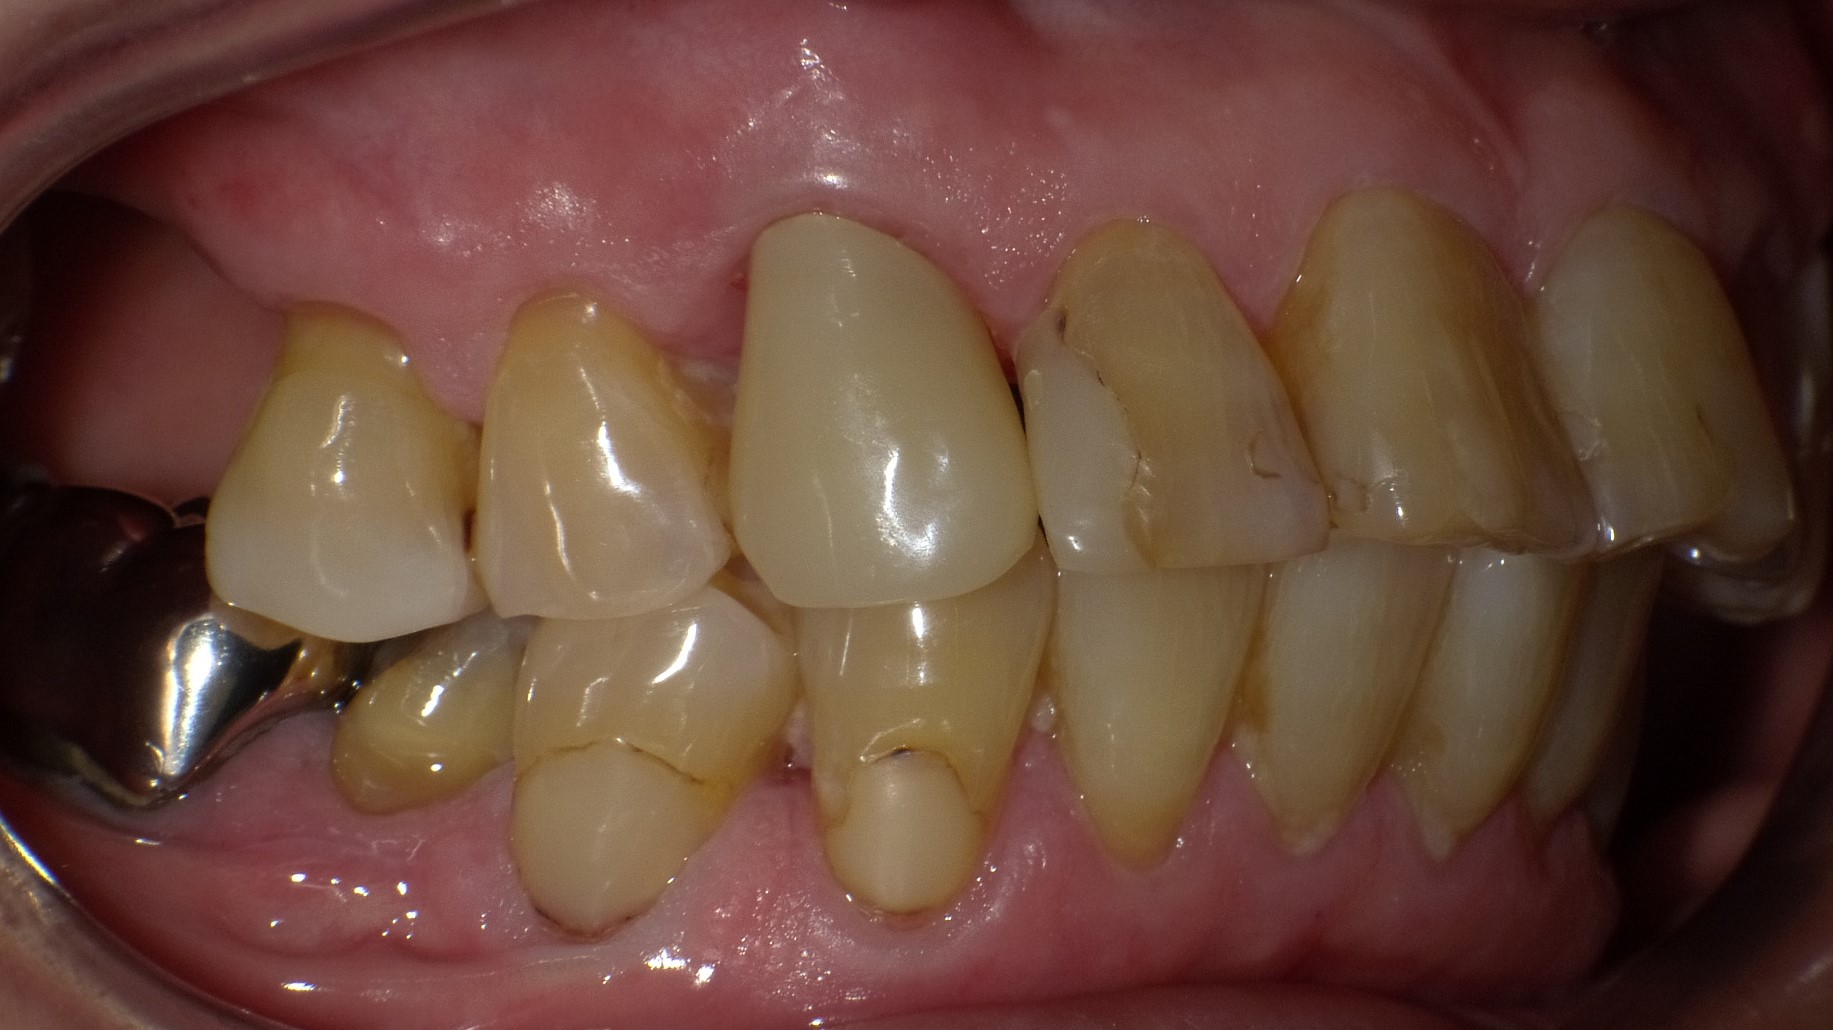

全周1mm程度、一回り小さく削った歯の上にセラミックで作った被せをすっぽり被せ、歯の色や形、歯並びなどをトータルに改善する方法です。セラミッククラウンは、歯を削ることで、表現や修飾の自由度が大きくなり、天然歯と同様あるいはそれ以上に見事な色合いや質感が出せるため、審美的効果が高い治療法です。

虫歯が大きく、その部分を取り除いたあと歯が少ししか残らない場合などにこの治療法を用います。歯にセラミックの冠を被せますので、ラミネートべニアより歯の形や大きさ、色調ともに表現の自由度が格段に広がりますが、歯を削る量は、それだけ多くなります。